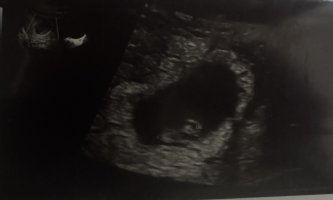

ja sitten odottamaan nt ultraa joka on 22.8